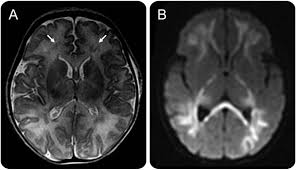

Lesions similar to cytotoxic edema, and lesions similar to vasogenic edema. Seizure, altered sensorium, fever frontal and temporal lobes, rarely extratemporal t2 hyperintensity, restricted diffusion, sometimes. Herpes encephalitis is the most common sporadic encephalitis in the united states and other industrialized countries .occurring as either a primary infection with herpes simplex virus or as a reactivation of latent virus, herpes encephalitis causes significant morbidity and mortality .early intervention with acyclovir significantly improves outcome; The clinical syndrome is often characterized by the rapid onset of fever, headache, seizures, focal neurologic signs, and impaired consciousness 1 . Having said that, mri with contrast is considered the most sensitive imaging modality, and findings are present in over half of individuals 8. The patients with the former type of lesions had fulminating disease, and were in severe clinical condition. Herpes simplex encephalitis occurs as 2 distinct entities: 4 it was found that, rather surprisingly, varicella zoster virus (vzv), the cause of chickenpox and herpes zoster, was the most frequently detected virus at 29%, with hsv and enteroviruses accounting for 11% of cases. Two subtypes are recognized which differ in demographics, virus, and pattern of involvement. (1)department of radiology, ankara numune education and research hospital, ankara, turkey. Neonatal herpes simplex encephalitis is caused by vertical transmission of infection during passage from birth canal with diffuse cerebral involvement within the first month after birth; As the older term limbic encephalitis implies, the most common location of involvement is the mesial temporal lobes and limbic systems, typically manifested by cortical thickening and increased t2/flair. In patients with herpes encephalitis, two distinct types of diffusion imaging findings (on b =1000 s/mm 2 images, and adc maps) were noted:

We present mri findings of two cases of herpes simplex encephalitis (hse) confirmed by pcr analysis, focusing on the serial changes after acyclovir therapy: 4 it was found that, rather surprisingly, varicella zoster virus (vzv), the cause of chickenpox and herpes zoster, was the most frequently detected virus at 29%, with hsv and enteroviruses accounting for 11% of cases. mri findings of herpes simplex encephalitis. For viral infection of the meninges, please refer to the general article on viral meningitis, and, for a broad view on the curriculum of infections of the central nervous system, refer to cns. The patients with the former type of lesions had fulminating disease, and were in severe clinical condition. The kappa value for interobserver agreement on rating the scans as normal or abnormal was good (0.65) for ct and moderate (0.59) for mri. Noguchi t, yoshiura t, hiwatashi a, et al. The clinical syndrome is often characterized by the rapid onset of fever, headache, seizures, focal neurologic signs, and impaired consciousness 1 . The patients with the former type of lesions had fulminating disease, and were in severe clinical condition. Specific diagnosis often requires pcr. As the older term limbic encephalitis implies, the most common location of involvement is the mesial temporal lobes and limbic systems, typically manifested by cortical thickening and increased t2/flair. In patients with herpes encephalitis, two distinct types of diffusion imaging findings (on b =1000 s/mm 2 images, and adc maps) were noted: A recent study in finland also used pcr to detect various viruses in the csf of over 3000 patients who had infections of the cns including encephalitis, meningitis, and myelitis.

(1)department of radiology, ankara numune education and research hospital, ankara, turkey. article in japanese yoshioka a, hirose g, tsukada k, oda r, kosoegawa h. Two subtypes are recognised which differ in demographics, virus, and pattern of involvement. Seizure, altered sensorium, fever frontal and temporal lobes, rarely extratemporal t2 hyperintensity, restricted diffusion, sometimes. Encephalopathy from herpes simplex encephalitis (hse). Specific diagnosis often requires pcr. Having said that, mri with contrast is considered the most sensitive imaging modality, and findings are present in over half of individuals 8. We present mri findings of two cases of herpes simplex encephalitis (hse) confirmed by pcr analysis, focusing on the serial changes after acyclovir therapy: